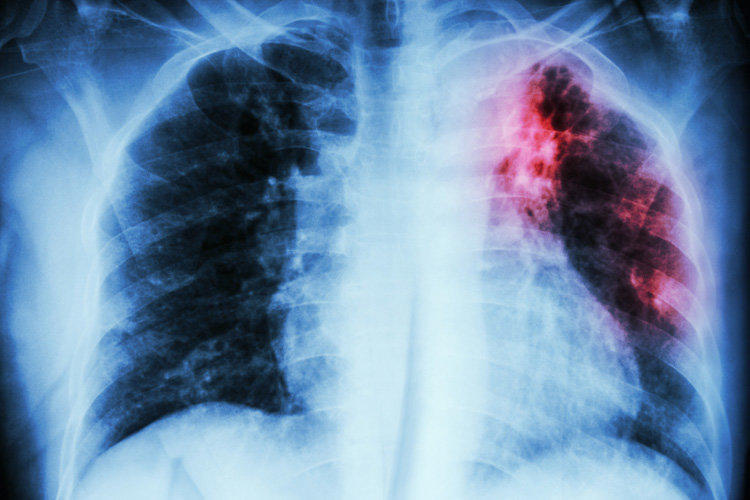

Кургак учук — кургак учуктун микобактериясы же Кох таякчасы та- рабынан пайда болуучу инфекциялык оору. Суйлешкенде, жетел- гөндө, чучкургенде аба аркылуу, ошондой эле байланыш-тиричи- лик жолу аркылуу кургак учукка каршы дары каражаттарын ичпеген адамдан жугат. Балдар учун кургак учук менингит жана диссемина цияланган туру сыяктуу, анын ете оор формаларынын тез арада еерчуп кетиши менен коркунучтуу. Кургак учук менингитинде жана инфекциянын диссеминацияланган формасында интенсивдуу тера пия жок болгон учурда ооруп калган бейтаптардын дээрлик барды гы кез жумушат.